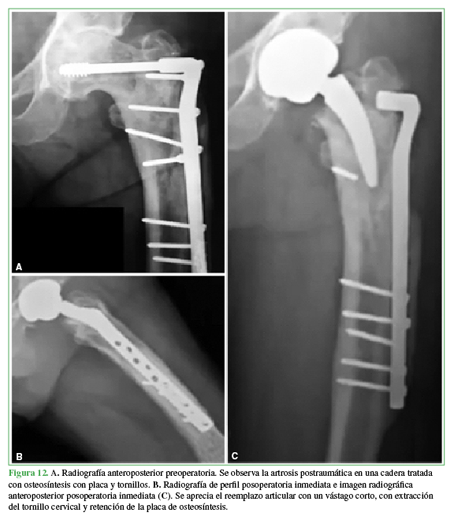

Las deformidades del fémur proximal pueden ocurrir en cualquier nivel. Asimismo, aumentan la dificultad técnica y presentan un elevado riesgo de complicaciones intraoperatorias, como fracturas o perforación cortical, sobre todo cuando existen elementos de osteosíntesis previos de larga data (Figura 12).

El tratamiento del paciente con una deformidad femoral proximal requiere criterio. Los esfuerzos para restituir la anatomía son imperativos, ya que las deformidades residuales no corregidas pueden tener consecuencias biomecánicas adversas. Hemos observado a lo largo de nuestra experiencia con vástagos cortos que dichos implantes evidencian ventajas en los casos con deformidades del fémur proximal, pueden evitar osteotomías femorales concomitantes o bien por tener la capacidad de insertarse evitando la extracción de implantes previos en forma total o parcial.45,77,78Adicionalmente, pueden compensar deformidades extrarticulares a nivel diafisario (más distales).